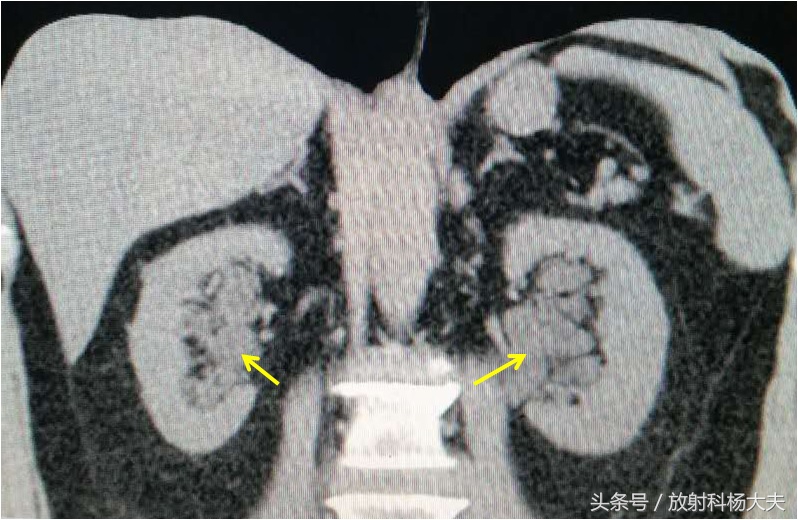

未注射对比剂时,双肾盂区可见液体密度,非常像肾积水